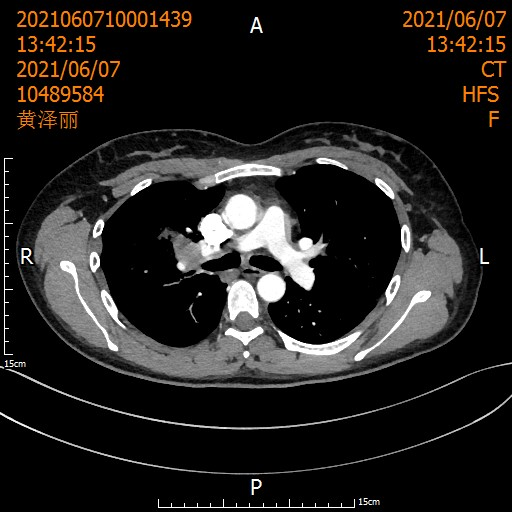

◆ 术后2周期“化免”联合4周期“免疫”巩固治疗——守护来之不易的胜利

◆ 定期门诊复查——像雷达般扫描复发风险